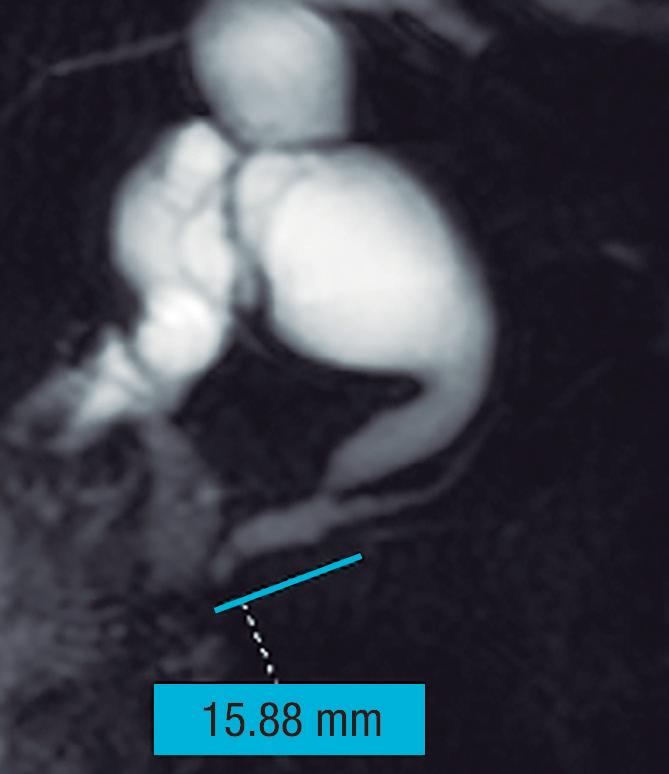

Conducto biliopancreático común largo

La unión entre el conducto colédoco y el conducto pancreático ocurre de diversas maneras, la mayoría son consideradas variantes normales y no tienen implicancias clínicas. Suelen confluir en un canal común con una longitud menor a los 5 mm y con un ángulo variable, alternativamente puede existir un ingreso al duodeno de ambos conductos por separado. En el canal común biliopancreático largo existe una unión precoz del colédoco con el conducto pancreático, con confluencia proximal al esfínter de Oddi por fuera de la pared duodenal. Para su diagnóstico se requiere una distancia mayor o igual a 15 mm entre la papila mayor y la confluencia de ambos conductos (Figura 6). Este conducto común largo permite el reflujo de las secreciones pancreáticas al colédoco, aumentando la presión intraductal y favoreciendo el desarrollo de quistes coledocianos. También favorece el reflujo de bilis hacia el conducto pancreático y, como consecuencia, predispone a la PA y PAR. 14,15

Figura 7. Conducto biliopancreático común largo

La flecha blanca señala la unión precoz del conducto colédoco con el conducto pancreático principal, alejada de la pared duodenal - papila mayor (cabeza de flecha), conformando un conducto biliopancreático común largo (> 15 mm).

A) Colangio-RM. La flecha señala la unión precoz del conducto colédoco con el conducto de Wirsung, alejado de la pared duodenal, conformando un conducto biliopancreático común largo. Se observa, como complicación, el desarrollo de un quiste de colédoco (cabezas de flecha). B) Colangio-RM magnificada. Medición de la distancia entre la pared duodenal, en el sitio de la papila mayor y la unión de los conductos colédoco y pancreático. C) Resonancia magnética, secuencia T1 con gadolinio, plano coronal. Unión de los conductos (flecha). Pared duodenal - papila mayor (cabeza de flecha).